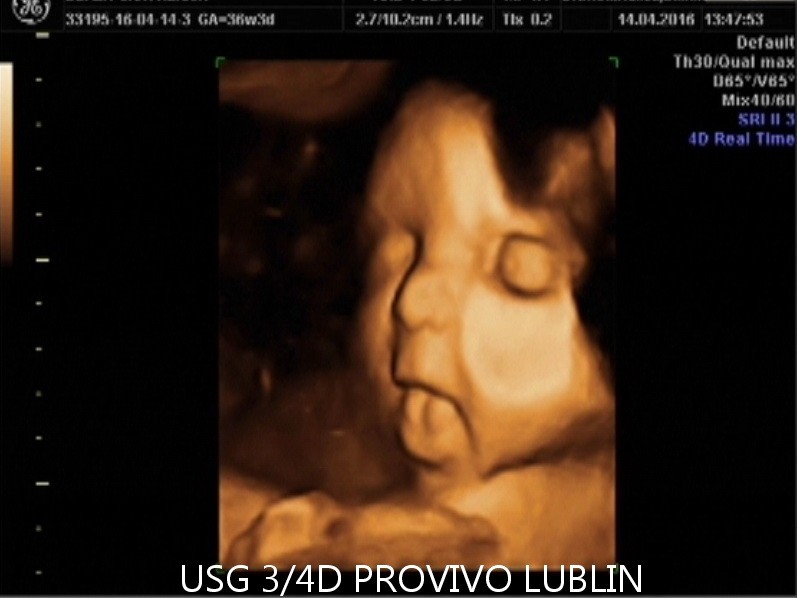

BADANIE USG 3/4D umożliwa dokładny wgląd w rozwój płodu, pozwala na podglądnięcie dziecka w sposób niemalże identyczny z jego aktualnym wyglądem.